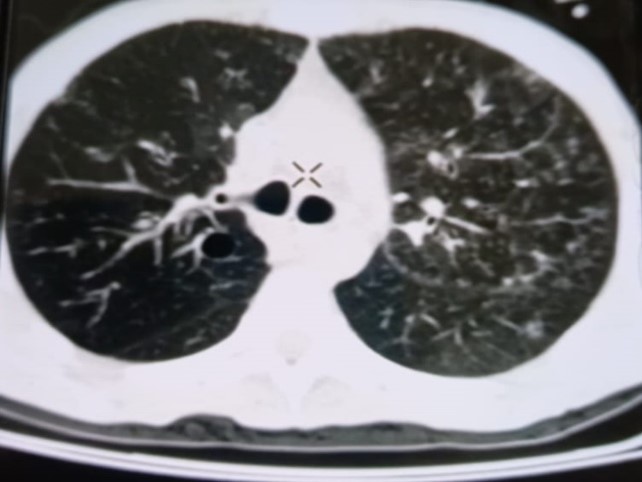

При проведении рентгенологического исследования органов дыхания в динамике спустя 2 недели с момента начала терапии данные компьютерной томографии высокого разрешения указали на следующие изменения: на фоне очаговой диссеминации в легких значительно увеличились по площади участки "матового стекла" в верхних долях обоих легких (описанные зоны неоднородные, сливные); площадь поражения легочной ткани - около 35-40%. В средних и нижних отделах легких с двух сторон выявлялись многочисленные перибронхиальные очаги до 3 мм в диаметре по типу «дерево в почках». В S 6 справа определялась зона альвеолярной инфильтрации. Выпот в плевральных полостях не определялся; внутригрудные лимфоузлы не увеличены. Заключение: признаки двусторонних полисегментарных интерстициально-инфильтративных, диссеминированных мелкоочаговых изменений легких, средняя вероятность вирусной пневмонии (в том числе COVID-19), в сочетании с диссеминированным процессом в легких (рис. 1-4).

Рисунок 1

Рисунок 2

Рисунок 3

Рисунок 4

Рис. 1-4. Компьютерная томограмма пациента Т., с ВИЧ: чередование участков «матового стекла» с диссеминированным процессом, инфильтрацией легочной ткани справа, наличие симптома «дерево в почках» (респираторный бронхиолит).